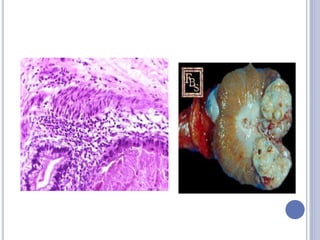

SEMINOMA

 Tumor más frecuente (35-50%)

 Se clasifica en:

- Tipo I (10%-bien diferenciado)

- Tipo II (60%-moderadamente diferenciado), “típico”

- Tipo III (30%- mal diferenciado), “anaplásico”

 Pacientes en la cuarta década de la vida.

 Son muy radiosensibles.

 36% tiene metástasis al momento del

Diagnóstico.

Seminoma espermatocítico:

 variedad del seminoma puro

 poco frecuente (2%)

 se observa sobre los 50 años

 comportamiento benigno aunque puede sufrir

transformación sarcomatosa

(rabdomiosarcoma).

Tumor de células redondas con moderada a intensa

cariomegalia y figuras binucleadas aisladas.

Anisonucleolosis. Abundantes mitosis